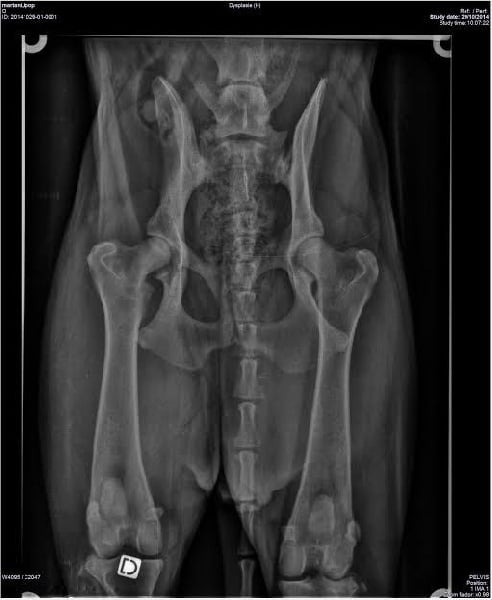

SCAU : Mention TRES BIEN radios des coudes : HD/A radios des hanches : HD/A |